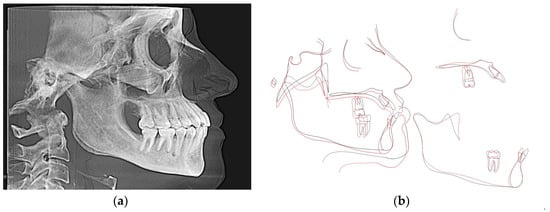

3.2.1. Cephalometric Radiographs and Analysis

| Measurement | Initial | Final | Norm |

|---|---|---|---|

| SNA (°) | 86.2 | 86.3 | 82 |

| SNB (°) | 86.7 | 86 | 80.9 |

| SN - MP (°) | 28.9 | 29.8 | 32.9 |

| FMA (MP-FH) (°) | 20.8 | 18.9 | 23.9 |

| ANB (°) | −0.5 | 0.3 | 1.6 |

| U1 - NA (mm) | 7.5 | 4.8 | 4.3 |

| U1 - SN (°) | 119 | 109.9 | 102.8 |

| L1 - NB (mm) | 9.4 | 3.7 | 4 |

| L1 - MP (°) | 106.3 | 87.4 | 95 |

| Lower Lip to E-Plane (mm) | 0.5 | −2.8 | −2 |

| Upper Lip to E-Plane (mm) | −6.8 | −6 | −6 |